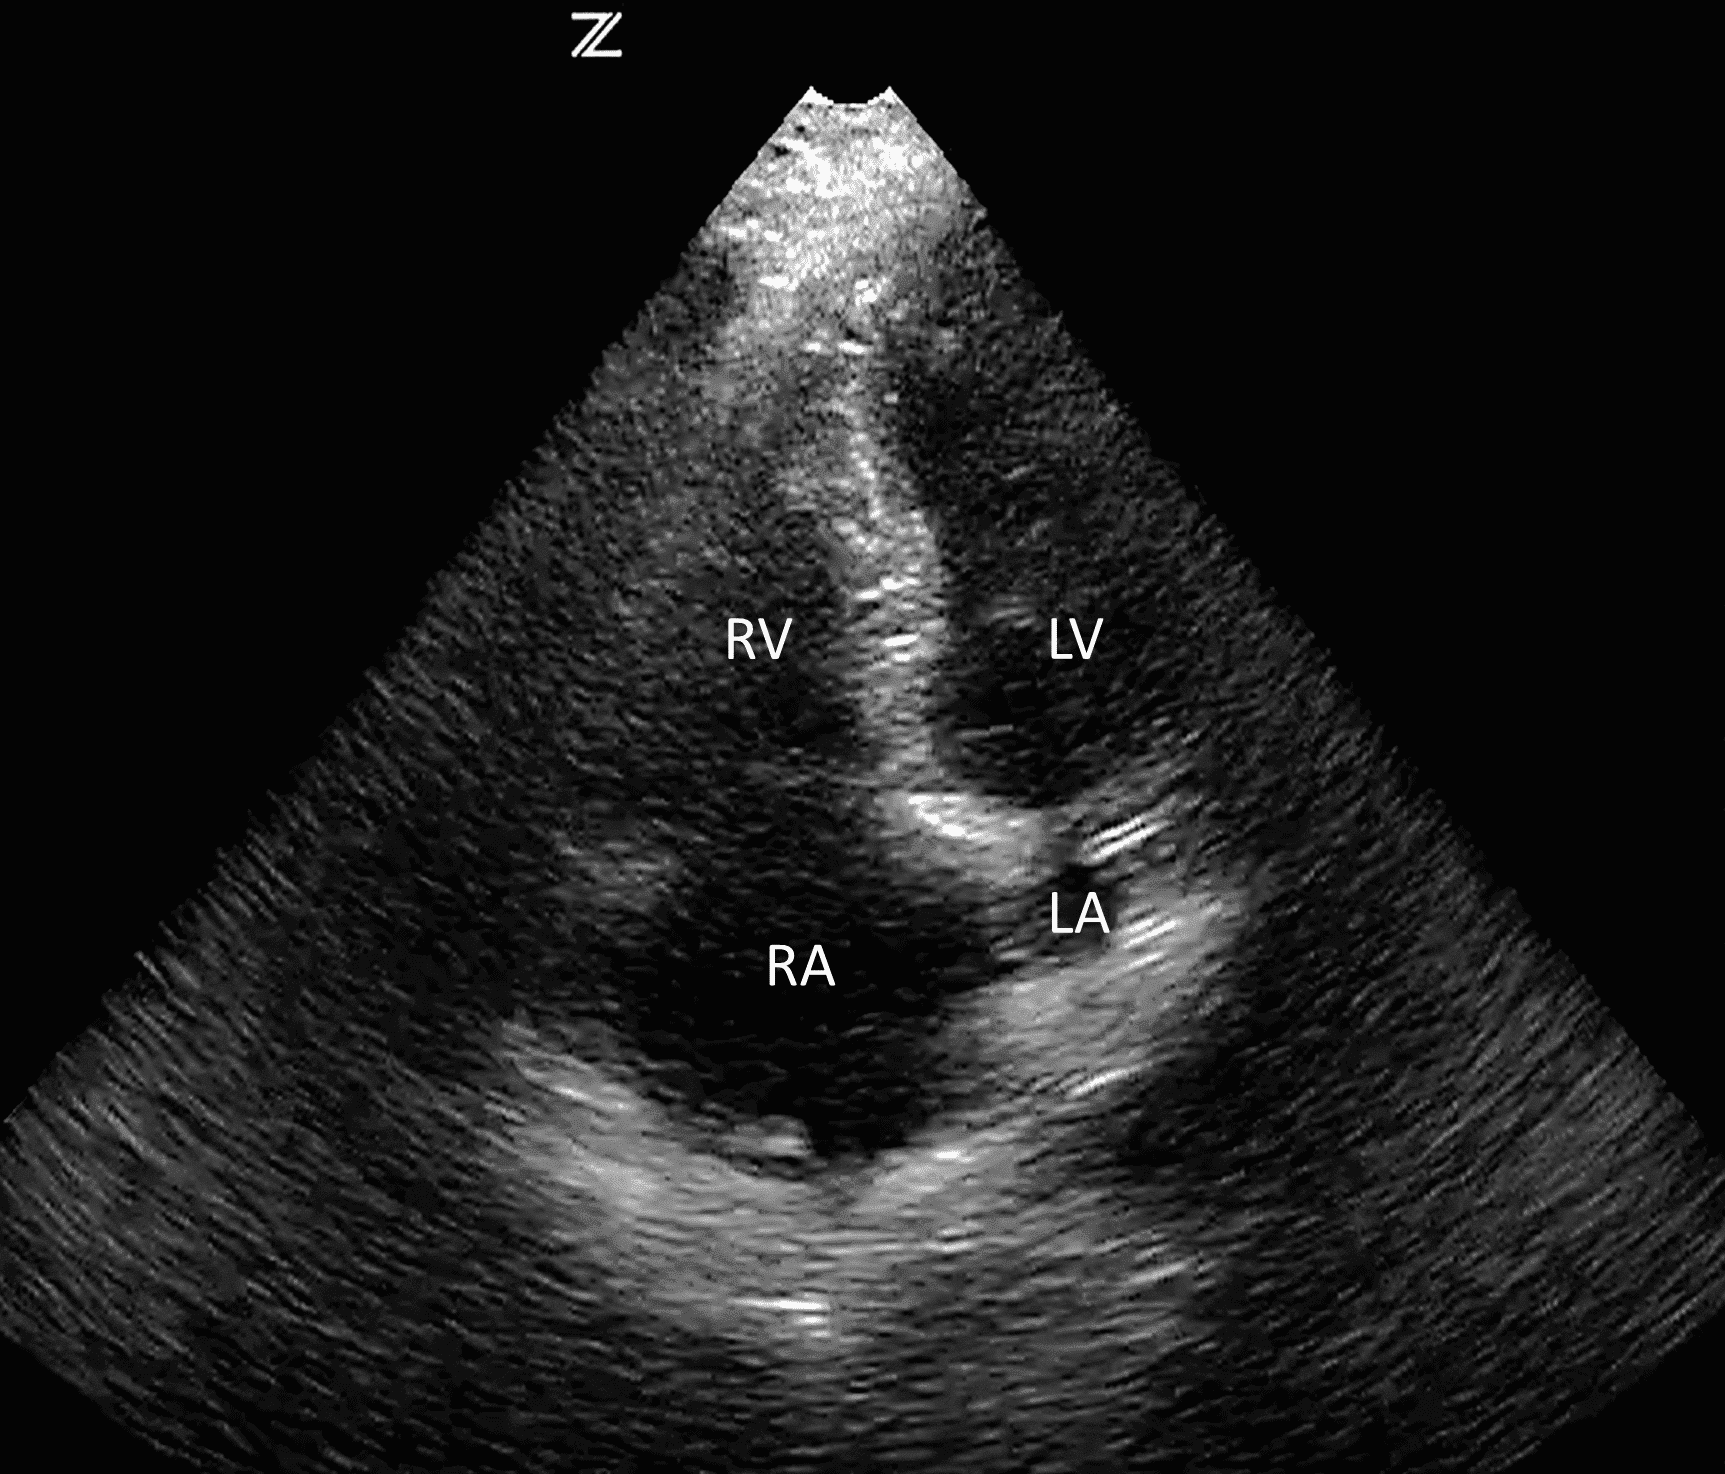

The apical four chamber view is obtained by placing the probe on the left chest at the level of the 4th or 5th intercostal space midway between the midclavicular and anterior axillary lines with the marker facing the patient’s right. Placing the patient in left lateral decubitus position may be necessary to acquire the apical four chamber view (Figure 4). This view also allows for evaluation of right ventricular collapse, pericardial effusion and cardiac function.

Normal four chamber pericardial view.

RV

(right ventricle), RA (right atrium), LV (left ventricle), LA (left atrium)